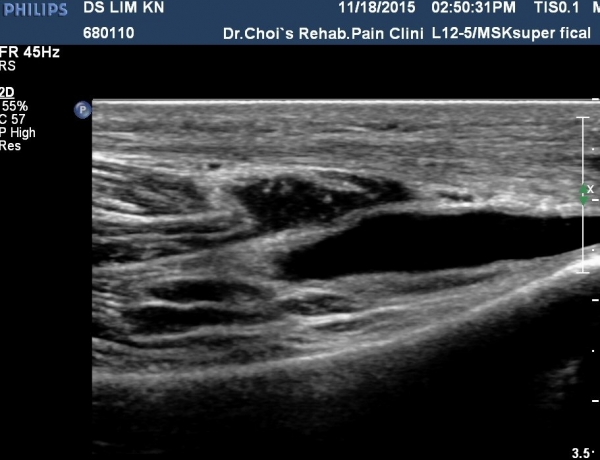

¹«¸­À§  ³»Ãø sartorius Ⱦ´Ü¸é°Ë»ç¿¡¼­ sartorius¿Í ³»Ãø ±¤±Ù »çÀÌ¿¡¼­ saphenous ½Å°æÀÇ ½½°üÀý ºÐÁö°¡ °üÂûµÊ(»çÁø 3).

ÃÊÀ½ÆÄ À¯µµÇÏ(»çÁø 5)¿¡ ½½°üÀý ºÐÁö ½Å°æÂ÷´Ü¼úÀ» ½ÃÇàÇÔ(»çÁø 4, ÷ºÎ µ¿¿µ»ó).